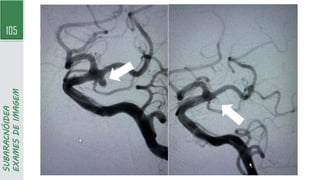

103 SUBARACNÓIDEA EXAMES DE IMAGEM A. HSA espessadifusa é observada na fissura inter-hemisférica anterior e nas fissuras sylvianas bilaterais, além da cisterna quadrigeminal. Identificou-se um aneurisma na artéria cerebral média esquerda B. HSA perimesencefálica; identifica-se apenas um pequeno foco de sangue na cisterna interpeduncular

• 104.

• 105.